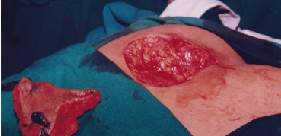

Radical Excision of the Sinus using Methylene Blue dye

Closure of Defect using Rotation Flap